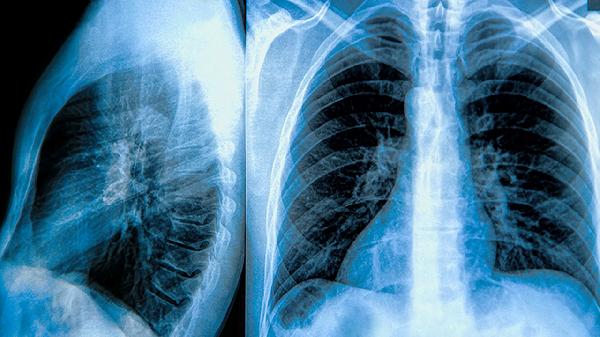

肺大泡患者宜常食百合银耳羹润肺,山药粥健脾,忌辛辣刺激食物。练习八段锦"调理脾胃须单举"和"左右开弓似射雕"两式,每周3次增强膈肌力量。保持环境湿度40%-60%,睡眠时采用45度半卧位减轻肺部压力。定期复查胸部CT监测肺大泡变化,若出现突发胸痛、咯血需立即就医。